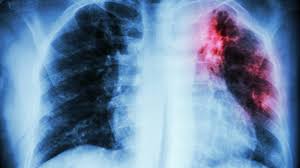

Mujer de 80 años con importante fibrosis pulmonar en rx de tórax el electrocardiograma con importante crecimiento y sibrecarga del ventrículo derecho por.